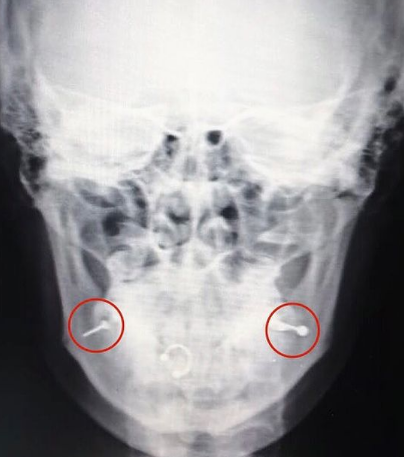

«Чтобы избежать послеоперационных рубцов на лице молодой девушки, врачи приняли решение оперировать со стороны слизистой путём продления имеющихся от пирсинга проколов. Штанги от пирсинга были обнаружены и удалены в первую очередь. Возникла сложность с извлечением металлического шарика, который ушёл в одну из щёк отдельно от остальной части пирсинга. Из-за сильного отёка шарик не прощупывался, на магнит не реагировал. Его расположение врачи увидели только на рентгене черепа: при открытии рта шарик снова смещался и ориентир терялся. Можно сказать, что эту деталь врачи искали вслепую», - отмечается в сообщении.